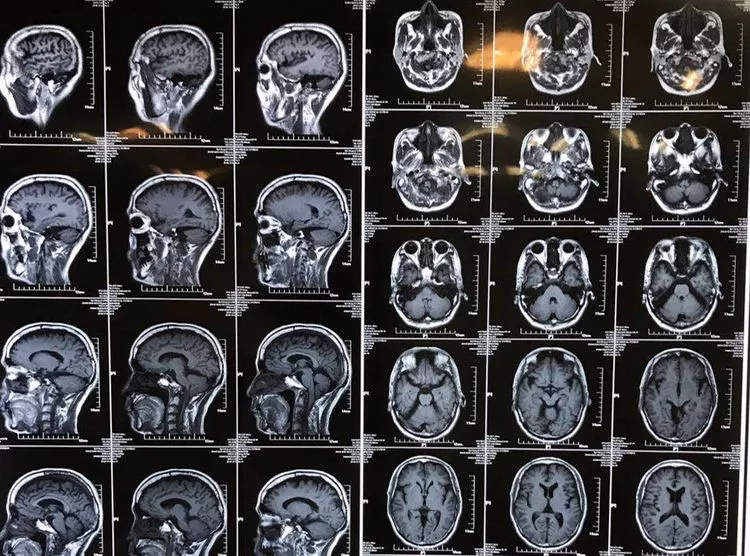

男性,59岁,半年前无诱因出现右半身麻木,伴右侧肢体乏力,右胸壁多汗,行走后右下肢抽痛明显,于当地医院就诊,查颈椎+胸椎+腰椎MRI示“颈髓脊髓空洞,腰4-5椎间盘突出”,对症治疗后症状无明显缓解。现为求进一步诊治,来西安交通大学第一附属医院,门诊以“脊髓空洞”收住入院。

入院查体:双侧瞳孔等大等圆,直径3.5mm,直接对光反射双侧灵敏,间接对光反射双侧灵敏。右颞顶枕部皮肤浅感觉减退,右侧躯体及右侧肢体皮肤浅感觉减退。左侧肢体肌力5级。右侧肢体肌力4级。右侧踝阵挛阳性。双侧Babinski征(+)。

影像学资料

1. Chiairi畸形并颈髓空洞

2. 脊柱侧弯

3. 腰4-5椎间盘突出